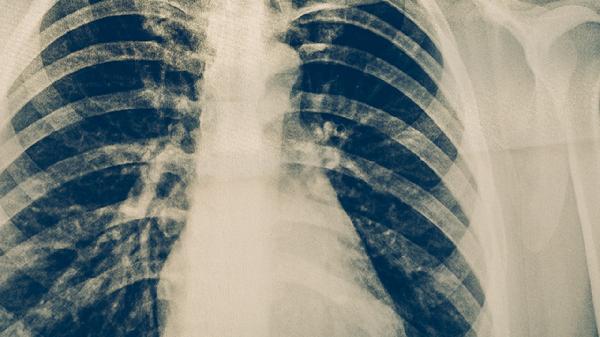

肺結(jié)核的化學(xué)治療主要通過抗結(jié)核藥物聯(lián)合用藥實現(xiàn),常用方案包括異煙肼片、利福平膠囊、吡嗪酰胺片、乙胺丁醇片和鏈霉素注射液等藥物組合。標(biāo)準(zhǔn)化療需遵循早期、規(guī)律、全程、適量、聯(lián)合的原則,具體方案由醫(yī)生根據(jù)病情制定。

肺結(jié)核化學(xué)治療期間應(yīng)保持均衡飲食,適當(dāng)增加優(yōu)質(zhì)蛋白和維生素攝入,避免飲酒和辛辣刺激食物。保證充足休息,進(jìn)行適度有氧運動增強(qiáng)體質(zhì)。嚴(yán)格遵醫(yī)囑完成全程治療,即使癥狀消失也不可自行停藥。定期復(fù)查胸部影像學(xué)和痰菌檢查,注意隔離防護(hù)避免傳染他人。出現(xiàn)藥物不良反應(yīng)時及時就醫(yī)調(diào)整方案,不可擅自更換藥物。